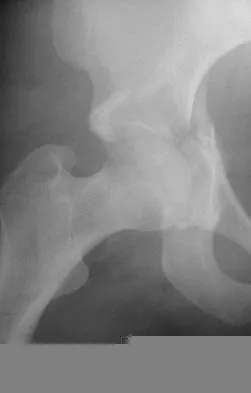

A 32-year-old woman with systemic lupus erythematosus treated with methotrexate and oral corticosteroids reports right groin pain with ambulation and night pain. Examination reveals pain with internal and external rotation and flexion that is limited to 105 degrees because of discomfort. Laboratory studies show a serum WBC of 9.0/mm3 and an erythrocyte sedimentation rate of 35 mm/h. Figures 5a and 5b show AP and lateral radiographs of the right hip. Further evaluation should include

Explanation

The radiographs show Ficat and Arlet stage 2 osteonecrosis. The femoral head remains round, and there are sclerotic changes in the superolateral quadrant. Patients with systemic lupus erythematosus are at risk for osteonecrosis because of prednisone use and the underlying metabolic changes associated with the condition (hypofibrinolysis and thrombophilia). MRI is the best diagnostic method for detecting osteonecrosis, with a greater than 98% sensitivity and specificity. For this patient, an MRI can assess the contralateral hip for any involvement and can quantify the extent of the lesion. Mont MA, Jones LC, Sotereanos DG, Amstutz HC, Hungerford DS: Understanding and treating osteonecrosis of the femoral head. Instr Course Lect 2000;49:169-185.

References: